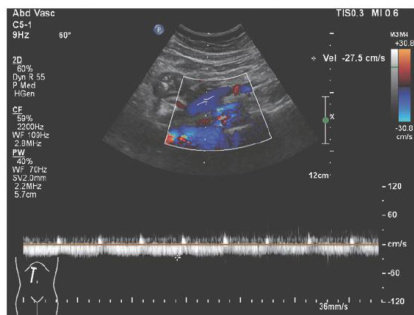

Abstract:Portalvein thrombosis (PVT)isacommonandseverecomplicationinpatients with livercirhosis,andalterations in portal hemodynamicsarecloselyasociated withthedevelopmentof PVT.The presenceof large spontaneoussplenorenal shunt (SSRS)maylead toreductionsin portalveinperfusionand bloodflowvelocity,whichmaycompromisetheanticoagulanteffecton PVT.This articlereports thetreatmentstrategiesofSSRSembolizationcombinedwithanticoagulanttherapythathelptoachieve completerecanalizationoftheportalvein;however,highqualityclinicalstudiesarestillneededtofurthervalidateandsupportthe effectiveness of this strategy.

门静脉血栓(portalveinthrombosis,PVT)是肝硬化患者常见的严重并发症之一,门静脉血流量减少是血栓形成的重要影响因素[1]。(剩余8399字)